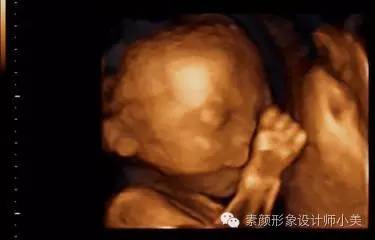

27周的胎儿现在体重已有900克左右,身长大约达到38厘米。可以看到胎儿头上已长出了短短的胎发。这时胎儿的听觉神经系统也已发育完全,对外界声音刺激的反应更为明显。你可以继续为他讲故事或者给他听音乐,这会让你和胎儿都感到平静和愉快。